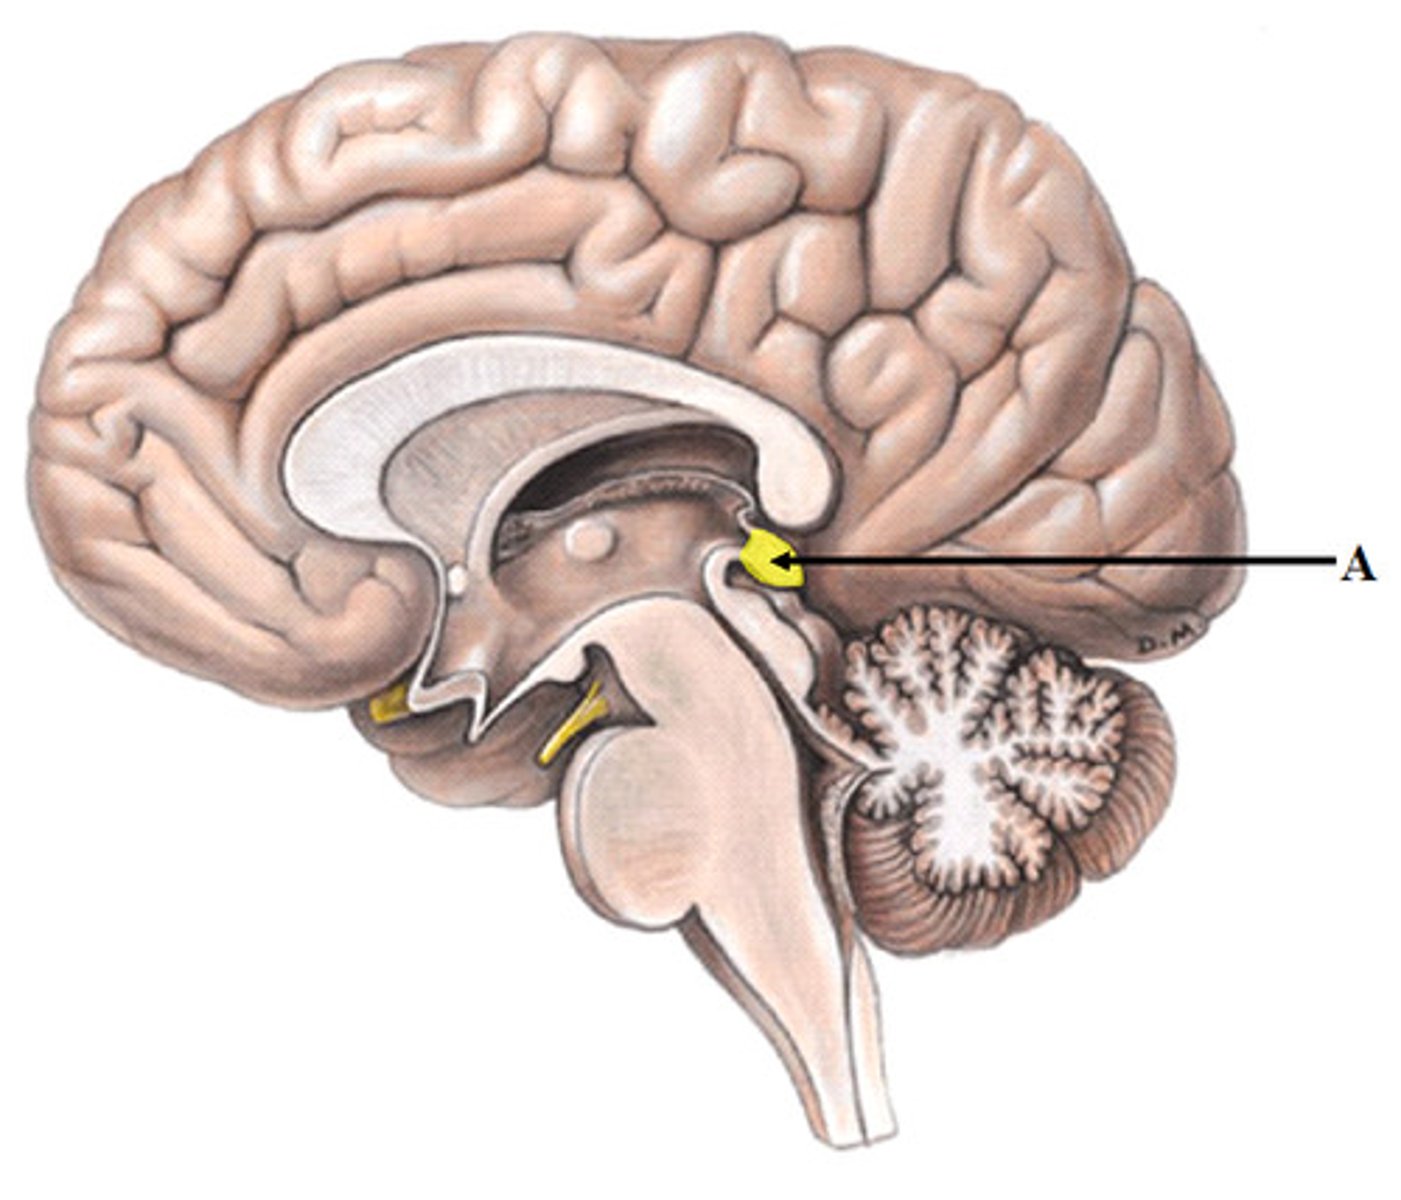

pineal body (pineal gland)

cerebral aqueduct (mesencephalic aqueduct)

interventricular foramen

third ventricle

thalamus

hypothalamus